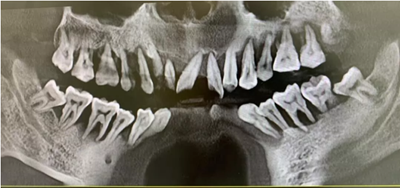

這是一個三十多歲的小伙子牙周炎的最終歸宿——全口牙松動,拔除。在口腔大夫那里,這些病例已經(jīng)司空見慣了,一句話形容:看起來,他們一顆牙也不缺,其實,已經(jīng)一顆牙也不在了!